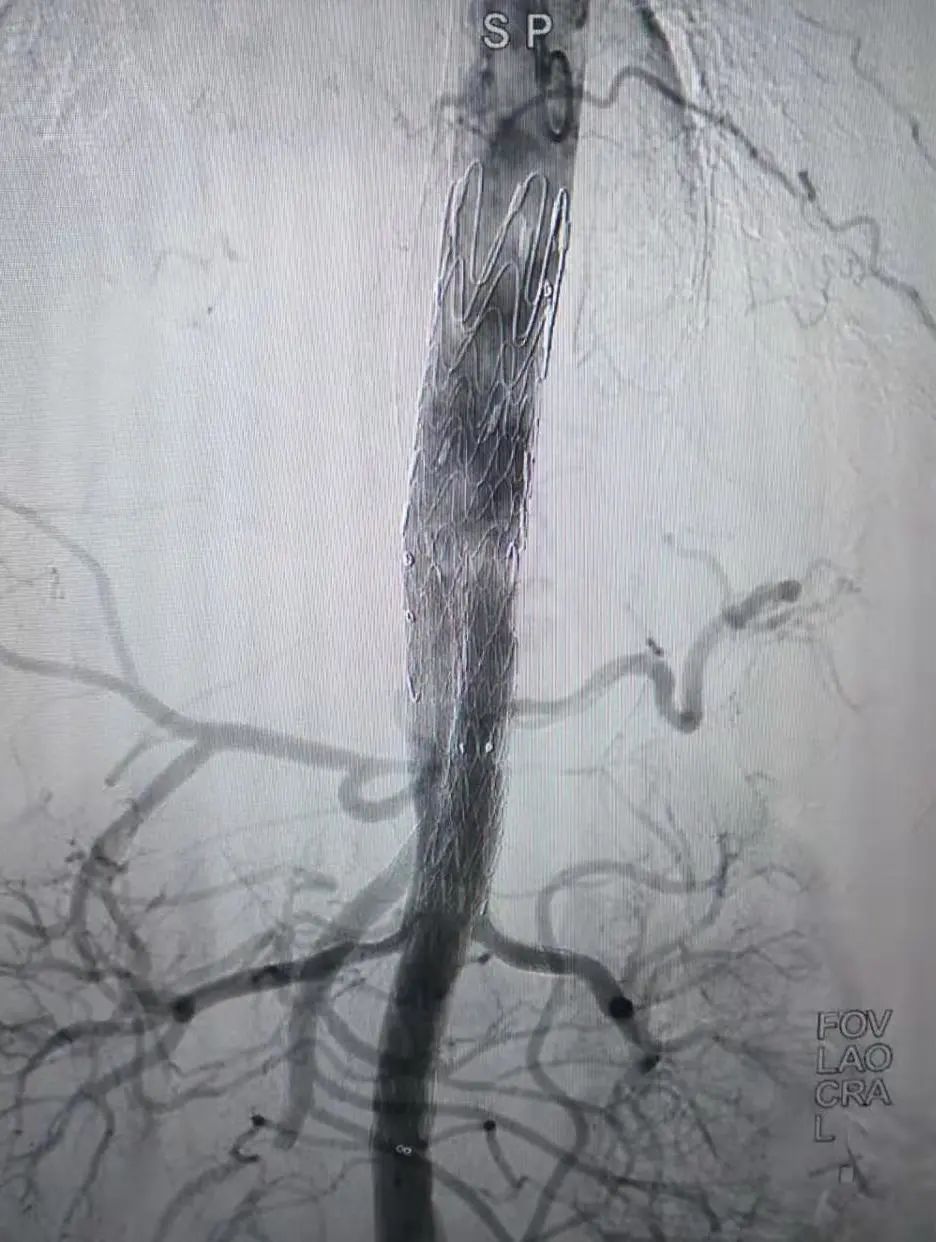

由于不同患者内脏动脉开口位置千差万别,如何进行支架定位并顺利置入分支覆膜支架是手术成功的关键。实际手术中,依据先进的术中导航技术,准确释放主体覆膜大支架后,顺利将覆膜小支架置入肠系膜上动脉、双肾动脉等分支动脉,另外一支接第二枚覆膜支架隔绝腹主动脉假性动脉瘤,从而既隔绝了动脉瘤,又保留了内脏血流(图 3,4)。

图 3

图 4